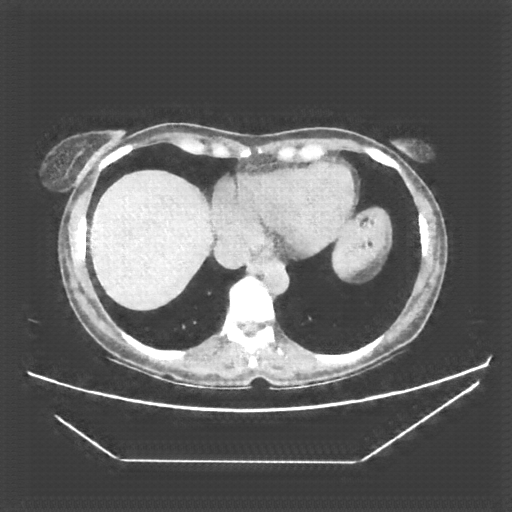

Original NATIVE CT scan (input)

No window - Raw intensity values

Lung window (WL -600, WW 1500 β†’ Low βˆ’1350, High +150)

Mediastinum window (WL 40, WW 400 β†’ Low βˆ’160, High +240)